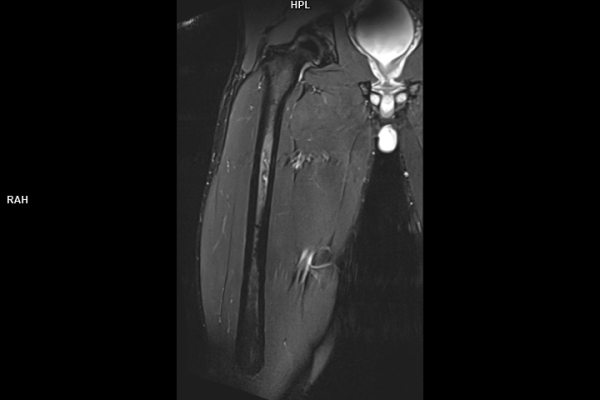

Detailbild MRT

• Muskuloskelettale Bildgebung

Die MRT (Magnetresonanztomographie) arbeitet mit Magnetfeldern und Radiowellen und eignet sich besonders für Untersuchungen der Weichteile wie Gehirn, Muskeln oder Gelenke. Die CT (Computertomographie) nutzt Röntgenstrahlen und liefert schnelle, hochauflösende Bilder, insbesondere für Knochen, Lunge oder innere Organe. Die Wahl der jeweiligen Untersuchung richtet sich an das individuelle Krankheitsbild und wird bei der Überweisung festgelegt.